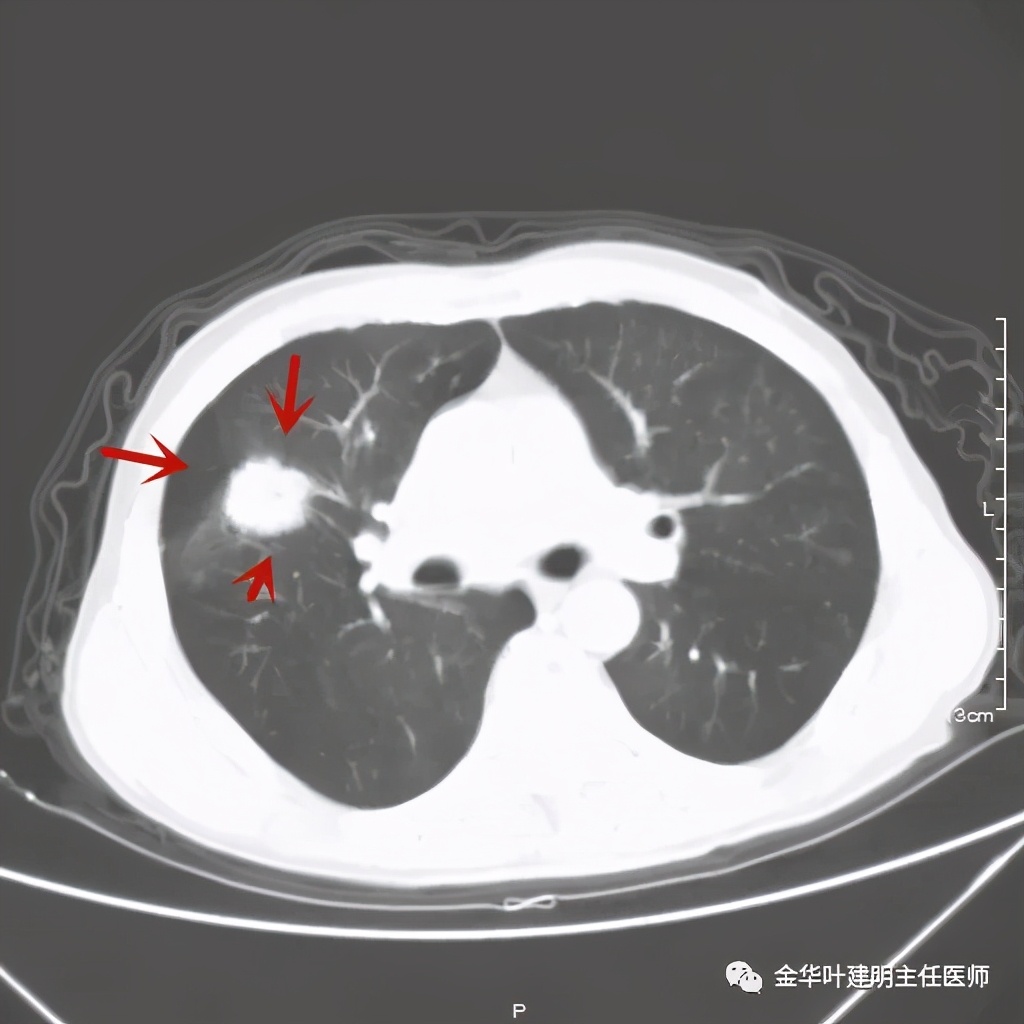

上图示病灶边缘不太光整,内部密度不太均匀

上图紫色箭头示叶间胸膜受牵拉,病灶边缘部分见到细毛刺